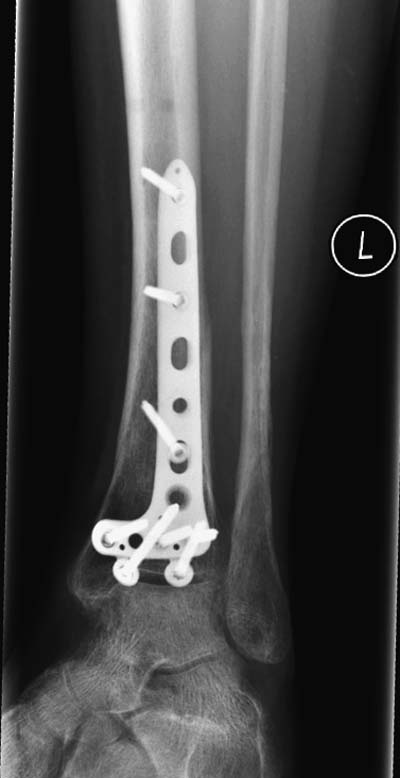

Первый случай, где перелом в результате падения с  небольшой высоты, где

мортиз рентген снимок показал отстутствие укорочения наружной

лодыжки и КТ срезы подсказали направления атаки. После такой фиксации

нет надобности в гипсовой повязке, брейс и через две недели движения в

суставе без нагрузки.